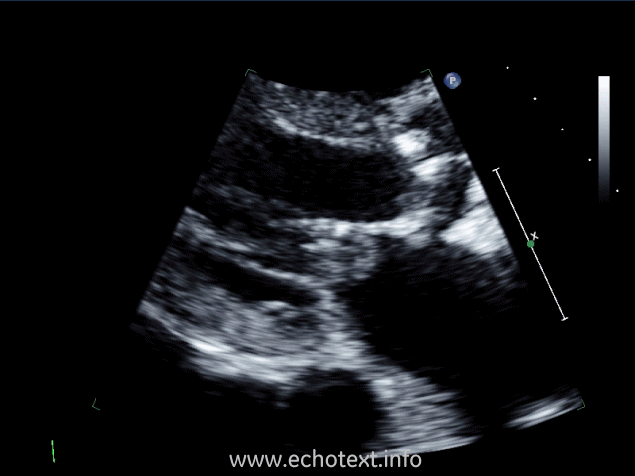

Which cardiac pathology is shown below?

Mitral annular calcification and AS

Mitral valve endocarditis and AS

Mitral stenosis

Constrictive pericarditis and AS

Mitral valve prolapse and AS